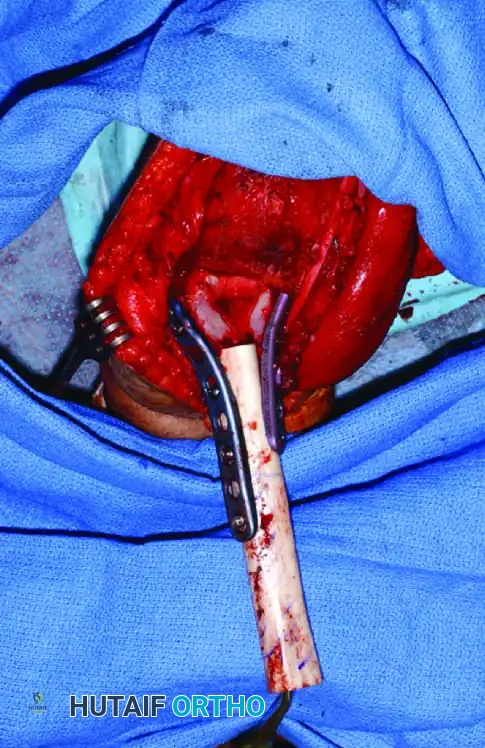

Following extended curettage, the structural integrity of the bone is compromised. The defect is typically reconstructed using PMMA cement, often augmented with internal fixation (screws or plates) to prevent pathological fracture.

Intraoperative view of a curetted cavity packed with PMMA cement and augmented with structural screws.

Postoperative radiographs demonstrating successful extended curettage, cementation, and screw augmentation of a distal tibial lesion.